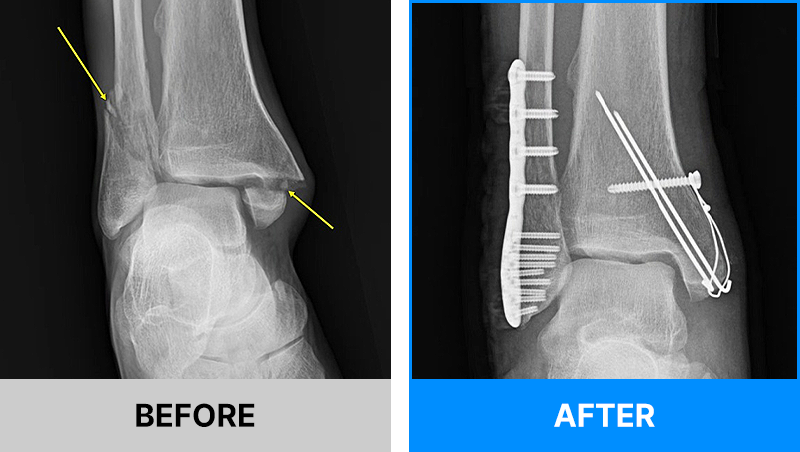

왜 당일 입퇴원 수술일까요?

오래 입원할 필요가 없기 때문입니다.

서울거탑정형외과에서는 전신마취, 척추마취가 아닌

국소부분마취(신경차단) 및 수면 마취를 통해 수술을 시행합니다.